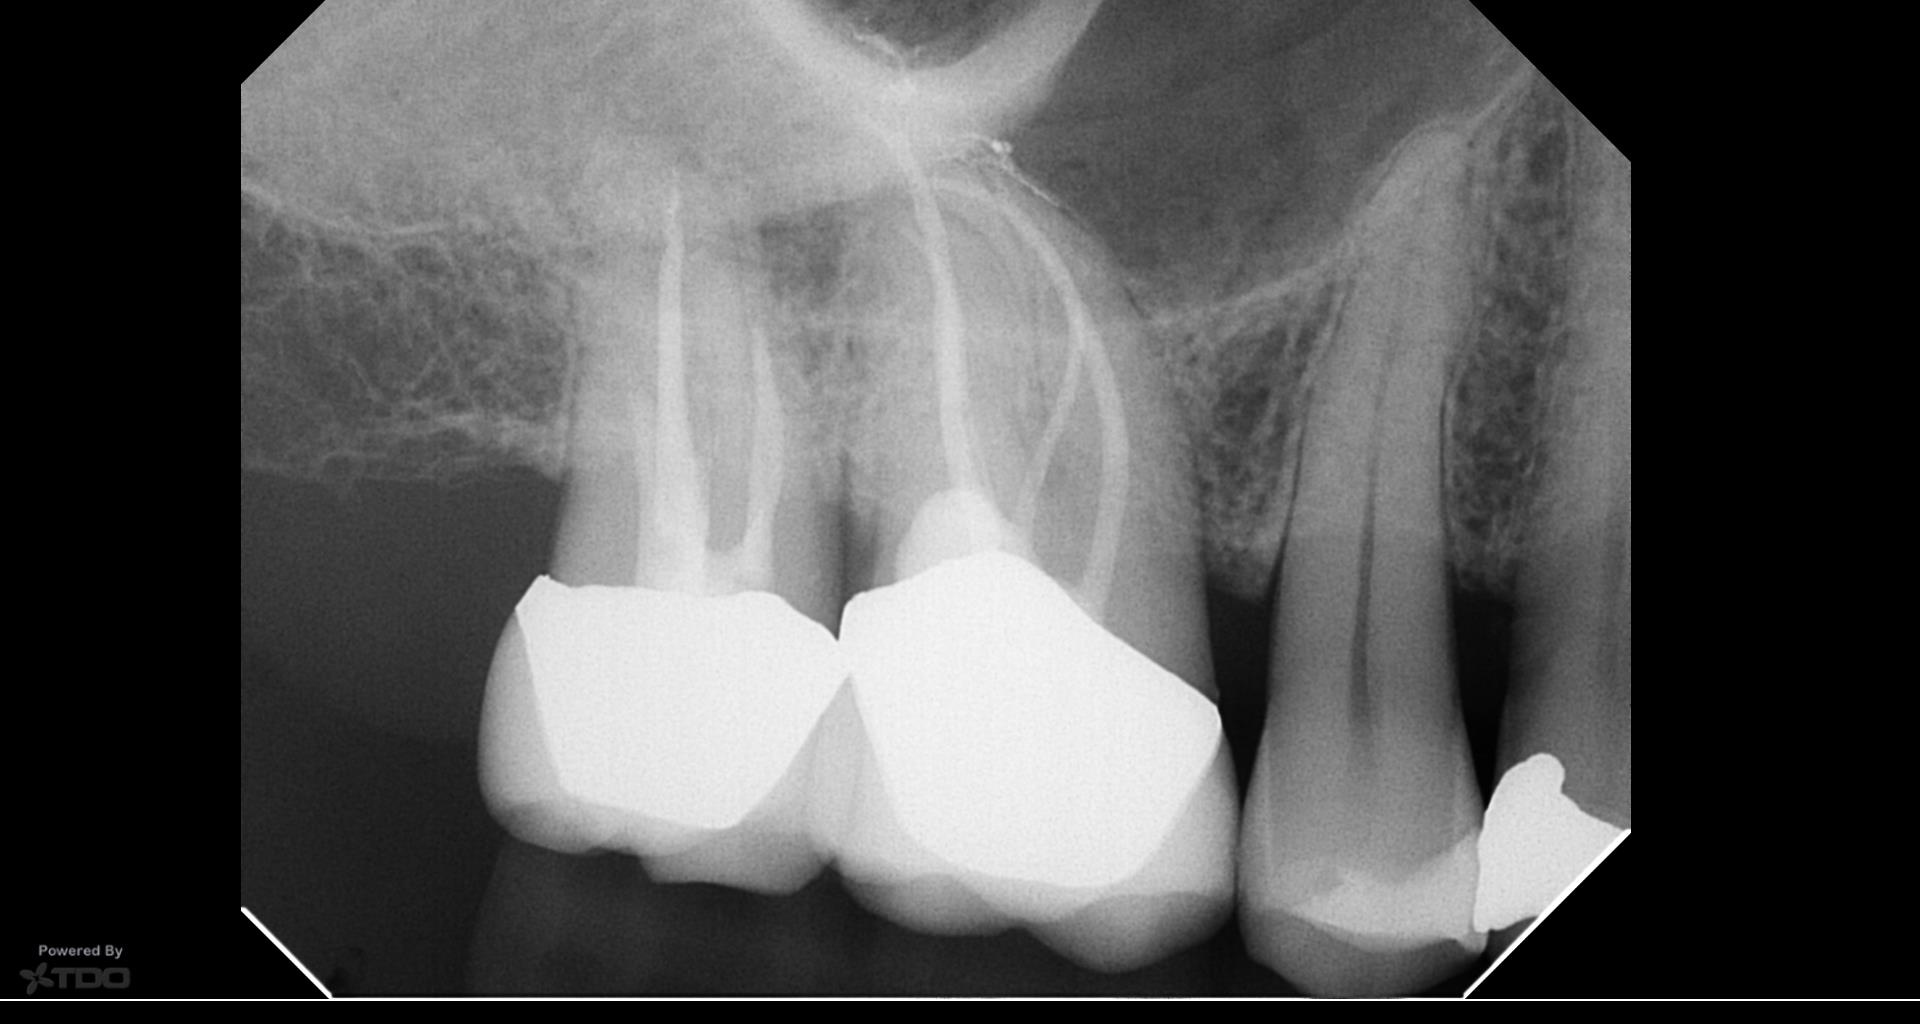

No apparent periodontal communication, treated internally. V-Tapers. Glass fibre post on the palatal canal

Hi Carlos, Thanks for posting. Looks like a very well treated case! However, I’m not sure if the pre-treatment diagnosis was 100% correct as it appears more like internal resorption in the images that you have shown. Pat

Thanks for posting. Looks like a very well treated case! However, I’m not sure if the pre-treatment diagnosis was 100% correct as it appears more like internal resorption in the images that you have shown.